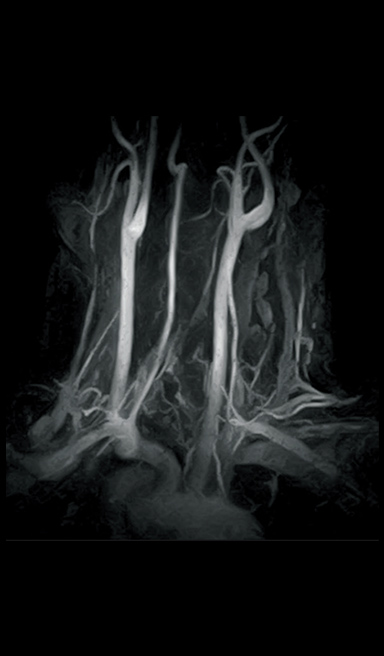

3D-VASC-ASL (Non-Subtraction technique)